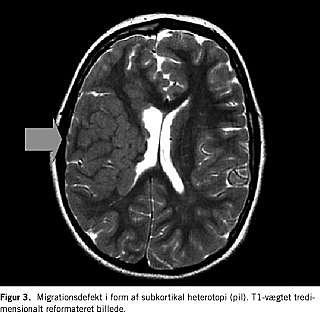

En hyppig årsag til neonatale kramper er hypoksisk-iskæmisk encefalopati. Herudover er der tale om strukturelt, metabolisk, infektiøs, abstinensudløst eller familiært betingede anfaldsfænomener. En grundig anamnese, klinisk vurdering, parakliniske undersøgelser inklusive lumbalpunktur er essentiel, men er årsagsforholdene usikre, spiller MR-skanning en vigtig rolle. Det kan dreje sig om strukturelle misdannelser, tegn på intrauterin infektion eller specifikke syndromforandringer (Figur 1 ). MR-skanning giver et væsentligt bidrag til en hurtig diagnostisk afklaring, hvilket i nogle situationer kan få behandlingsmæssige konsekvenser, allerede mens barnet ligger på neonatalafsnittet. I tilfælde af hypoksisk-iskæmisk hjernepåvirkning kan omfanget af de hypoksiske skader påvises umiddelbart efter skadens optræden med MR-skanning ved hjælp af såkaldte diffusionsoptagelser (en afbildning af vandets molekylbevægelser) [1] (Figur 2 ). Med spektroskopi kan man bedømme graden af neurontab og graden af anaerobt stofskifte [1], hvilket er vigtige prognostiske indikatorer. Undertiden afslører man med spektroskopien abnorme metabolitter, og det kan i disse situationer give en vigtig vejledning i påvisningen af en metabolisk sygdom. CT bør som hovedregel ikke anvendes i neonatalperioden undtagen i helt specielle tilfælde for at påvise store, behandlingskrævende blødninger på tidspunkter, hvor der ikke er mulighed for at foretage en MR-skanning.

Centralnervesystemets udvikling kan som bekendt groft inddeles i seks faser, neurolations-: kanalisations-, proliferations-, migrations-, organisations- og myeliniseringsfasen, hver med sine karakteristiske udviklingsanomalier. De hyppigst forekommende luknings- og kanalisationsanomalier, encefalocele, myelomeningocele, Dandy-Walker-malformation og holoprosencefali volder ikke de store diagnostiske vanskeligheder og kan afsløres ved både CT og MR-skanning [1]. MR-skanning er dog at foretrække i disse udredninger, da man ved CT har svært ved visuelt at erkende fossa posterior- og midtlinjeforandringer detaljeret, og man med MR-skanning i modsætning til CT kan afsløre, om der er ledsagende udviklingsforstyrrelser i faserne 3-6. Ud fra de strukturelle forandringer kan man fastslå tidspunktet for en eventuelt udefrakommende påvirkning. Er udviklingsforstyrrelsen betinget af en genetisk defekt, vil der ofte ske en påvirkning af flere faser i hjernens udvikling, hvilket resulterer i, at der eksempelvis både er migrationsdefekter og myelinforandringer [2]. Typeinddeling af migrationsdefekter, hvilket kun er muligt at foretage med MR, er essentiel i den neuropædiatriske udredning. Dels er migrationsdefekter hyppigt forekommende ved mental retardering, epilepsi og cerebral parese, dels er nogle mønstre syndromspecifikke [2].